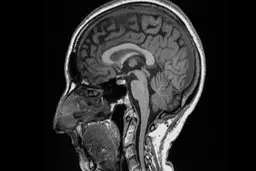

کرونا | مغز | اسکن مغزی | واکسن کرونا

کووید باعث چه تغییراتی در مغز میشود؟

نتایج یک مطالعه نشان می دهد که ابتلا به بیماری کووید-۱۹…